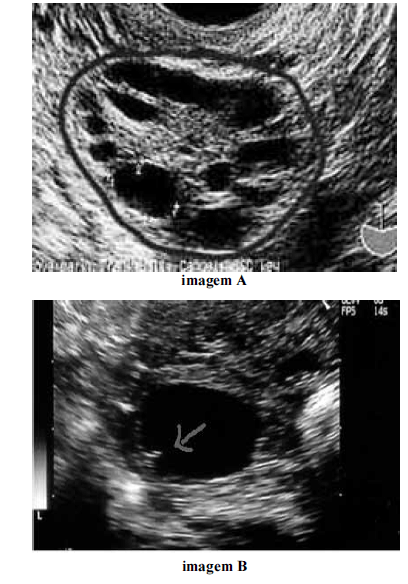

Considerando as imagens ovarianas apresentadas acima, julgue os itens a seguir.

Pacientes portadoras do distúrbio endócrino que cursa com os ovários representados na imagem A possuem maior risco de apresentar síndrome de hiperestimulação ovariana.